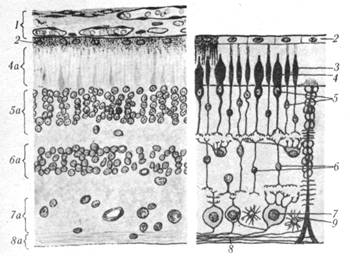

Рис. 2.2. Сосудистая оболочка (внутренняя поверхность):

1 — ресничный кружок; 2 — ресничный венчик; 3 — склера; 4 — ресничные отростки; 5 — сетчатка; 6 — хрусталик.

Рис.2.4. Строение сетчатки глаза:1— сосудистая оболочка глазного яблока: 2 — пигментный эпителий сетчатки; 3 — палочки; 4 — колбочки; 4а — слой палочек и колбочек; 5 — ядра палочек и колбочек; 5а — внешний ядерный слой сетчатки; 6 — биполярные клетки; 6а — внутренний ядерный слой сетчатки; 7 — ганглиозные клетки; 7а — ганглиозный слой; 8 — аксоны ганглиозных клеток; 8а — слой нервных волокон; 9 — астроцит.

Сетчатая оболочка, или сетчатка (retina) (рис.2.4), выстилает глазное яблоко изнутри и делится на переднюю (меньшую) слепую и заднюю (большую) зрительную части. Границей между этими частями является хорошо видимый на препарате простым глазом зазубренный край (oraserrata). Зрительная часть сетчатки (parsoptica) построена очень сложно, но невооруженным глазом в ней можно различить лишь два слоя: пигментный (stratumpigmenti), плотно срастающийся с сосудистой оболочкой, и мозговой (stratumcerebrate), обращенный в сторону стекловидного тела. Микроскопическое изучение мозгового слоя сетчатки позволяет выделить в нем несколько слоев, содержащих светочувствительные рецепторные аппараты (палочки, колбочки), а также ганглиозные и биполярные клетки.

На внутренней поверхности сетчатки имеется видимый простым глазом небольшой (около 1,5 мм в диаметре) диск зрительного нерва (discus. optici) суглублением в центре. Он является местом, где собираются аксоны ганглиозных клеток сетчатки и, прободая сосудистую оболочку и склеру, образуют зрительный нерв. Область диска лишена светочувствительных элементов (слепое пятно). Несколько кнаружи от диска зрительного нерва заметно округлое (около 1 мм ) красновато-коричневого цвета пятно (macula) — место наиболее острого зрения.